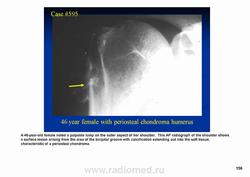

Периостальная хондрома (син.: юкстакортикальная хондрома, паростальная хондрома редкая доброкачественная опухоль, состоящая из зрелой хрящевой ткани и расположенная над надкостницей. Обычно она разрушает наружную часть коркового слоя, но не прорастает в костно-мозговой канал. Мужчины болеют в два раза чаще женщин. Типичная локализация - проксимальный конец плечевой и бедренной кости дистальный конец бедренной кости, а также фаланги. В редких случаях одновременно поражается несколько костей. Периостальная хондрома обнаруживается большей частью в метафизарной части, лишь у 30 % больных поражаются диафизы. Опухоль достигает в среднем 2-3 см в диаметре. Она окружена зоной остеосклероза и сопровождается периостальным остеогенезом, так что на границе опухоли с костью образуется грушевидное углубление с четкими контурами. Под микроскопом периостальная хондрома имеет тонкие контуры, она как бы погружена в корковый слой и покрыта надкостницей, как тонкой скорлупой. На разрезе ее ткань синюшно-серая или белая, хрящевые элементы обладают дольчатым строением. Участки обызвествления имеют вид желтовато-белых вкраплений. Эта опухоль состоит из гиалинового хряща, дольки которого разделены фиброзными прослойками или костными балками, местами обызвествленными. Кое-где отмечается проникновение опухолевых клеток в костномозговой канал, на большем же протяжении внутренний контур образован компактной костью.

Дифференциальная диагностика представляет известные трудности в тех случаях, когда периостальная хондрома имеет сходство с юкстакортикальной хондросаркомой.